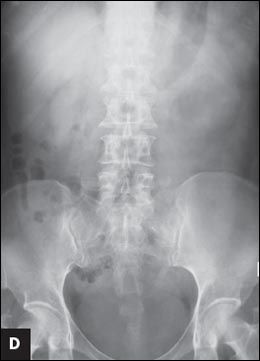

). Complete stone clearance is achieved after the third PCNL (

D

).

The patient underwent transurethral incision of the right ureterocele and ureteroscopic removal of the ureteral stone. Simultaneous right percutaneous nephrolithotomy (PCNL) was performed, and a ureteral stent was inserted at the end of the procedure (Figure 1B). Second stage right PCNL for the residual stones was performed 2 weeks later, and all the stones were cleared (Figure 1C). Left PCNL was also performed with clearance of all the residual stones (Figure 1D). Stone analysis revealed that the calculi were composed of 76% magnesium ammonium phosphate (struvite) and 24% calcium carbonate apatite.